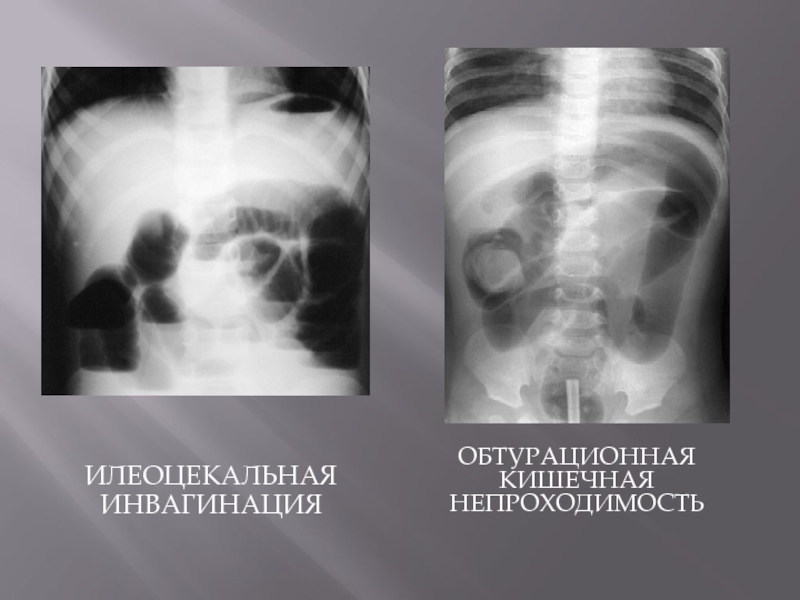

Иллюстрации и информация о симптомах острого кишечного непроходимости